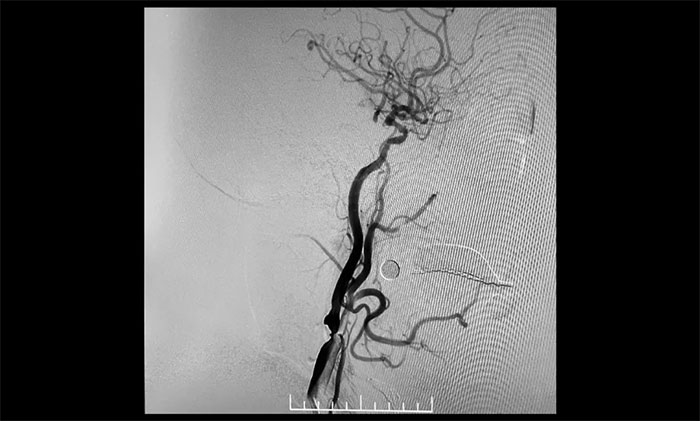

▲ 右颈内动脉起始段重度狭窄

排除手术禁忌,充分完善手术预案并获得家属同意后,9月4日,席刚明教授、王贵平博士顺利为患者进行了脑保护伞下右侧颈动脉支架置入手术,经皮右侧颈动脉球囊扩张成形术。